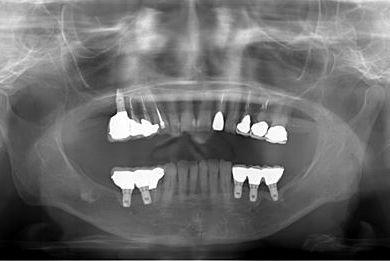

骨再生インプラント治療+セラミック治療

| カテゴリー | 【インプラント治療】【セラミック治療】 | ||||||||||||||||||||||||||||||||

| 性別/年齢 | 女性 / 53歳 | ||||||||||||||||||||||||||||||||

| 主訴 | 上のかぶせた歯にすき間があいてきた。インプラント治療も検討したい。 | ||||||||||||||||||||||||||||||||

| 治療内容 | インプラント6本(ソケットリフト)、ハイブリッドセラミック14本(ハイブリッドセラミック用土台5本、遊離歯肉移植術 | ||||||||||||||||||||||||||||||||

| 総治療費 | 2,751,445円 | ||||||||||||||||||||||||||||||||

| 治療期間 | 2年3ヶ月 |